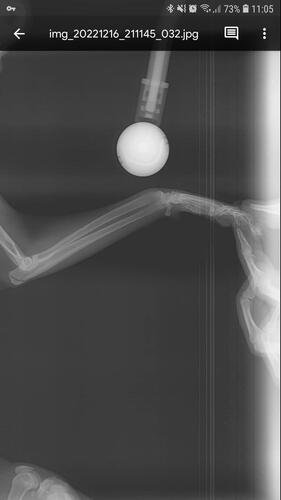

Depois de algumas consultas e até mesmo um diagnóstico errado, enfim descobriram que eu estava com as patinhas fraturadas, e pela forma como estavam a explicação era apenas uma: fui mais um alvo da maldade humana.

Eu preciso operar as patas o quanto antes, pois venho tendo perda óssea e mal consigo usar minha caixa de areia. Vivo apenas deitada e é minha mãe quem me alimenta e me da água na boca, além de levar na caixina, pois como podem ver nas fotos, minhas patas estão tortinhas e não consigo mais o mínimo de apoio.